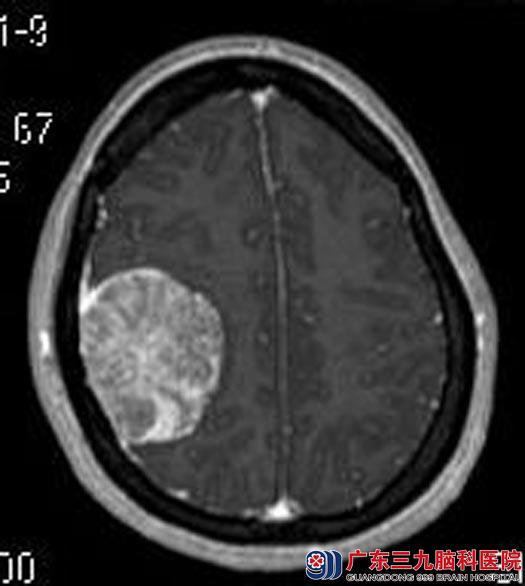

两年多的头晕,一直以为是颈椎病,竟然发现是脑肿瘤,家人立即带着她来到广东三九脑科医院。头颅MR检查提示右侧额顶部大脑凸面占位性病变,大小约46mm×55mm×49mm,考虑脑膜瘤可能性大。

确诊后,王女士要求手术切除治疗。由综合神经外科鲁明主任主刀在全麻下行右额顶脑膜瘤切除术,术中导航定位肿瘤体表面积,显微镜下见肿瘤呈灰白色,质韧、血供一般,边界清,镜下顺利全切肿瘤。术后王女士未出现语言、肢体等功能障碍。术后病理结果:纤维型脑膜瘤(WHO I级)。